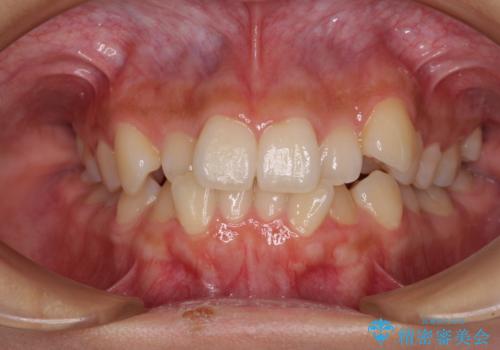

下の歯のがたつき 上より気になる

口元大事です! 見違える矯正!! 乱ぐい歯もあきらめないでください。